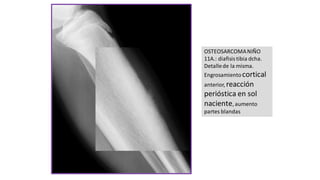

OSTEOSARCOMANIÑO

11A.: diafisis tibia dcha.

Detallede la misma.

Engrosamientocortical

anterior, reacción

perióstica en sol

naciente, aumento

partes blandas